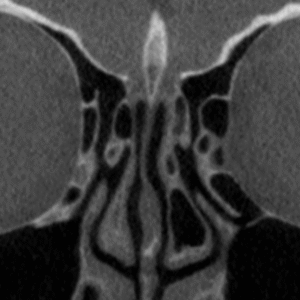

Anatomia cirúrgica e radiológica dos seios paranasais

Sinusotomias Maxilar, Etmoidal, Esfenoidal, Frontal

O Curso Endobrasília chega à sua terceira edição, consolidado como uma das principais imersões em cirurgia endoscópica nasal do país. Sempre muito bem avaliado pelos alunos, destaca-se pela combinação de conteúdo teórico de excelência, professores altamente dedicados e treinamento prático personalizado, proporcionando uma experiência completa e transformadora para otorrinolaringologistas e residentes.

No módulo teórico, os participantes terão acesso a aulas ministradas por especialistas reconhecidos, abordando técnicas cirúrgicas atualizadas, dicas fundamentais e estratégias para identificação segura dos reparos anatômicos essenciais. Essa base sólida prepara o aluno para executar as intervenções com segurança, precisão e maior confiança.